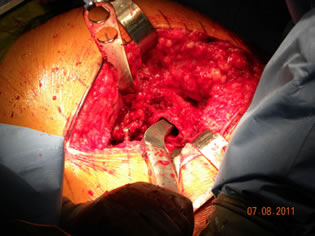

Dr. Testerman's Case

Dr. Testerman's cas is a forty-five year old female, morbidly obese with bilateral hip disease. She is currently household ambulatory and otherwise confined to a wheel chair, although able to independently transfer herself to and from bed. X-rays show destructive bilateral OA of the hip with such severity it is hard to determine if the underlying disease is hip dysplasia or not. The right hip head has collapsed making true measurement of femoral offset difficult.

Due to her relative young age, body weight and the likely fact that she will be facing one or more revisions in her lifetime Dr. Testerman decided a more bone conservative tissue sparing approach would be in her best interest. Although her body weight certainly did not lend itself to a conservative soft tissue approach this device does not require resection into the greater trochanteric and abductor musculature area.

At 5' 2" and 250 lbs this was going to be a challenge for any approach, devise, and surgeon. In addition this was being done at a new hospital with a new team that had not seen this devise before. Prior to surgery, John and I had a chance to review the x-rays and we did not see anything that should hinder the selection of the ARCTM Stem. We did have a conventional stem on backup and always recommend that a conventional stem be available. I did suggest that he take an intraoperative x-ray once the trials were implanted.

Trial stem was easily inserted. The acetabular preparation was carried out. |

| There was no difficulty with the trial femoral stem in place for either preparation or insertion of the acetabular component. |